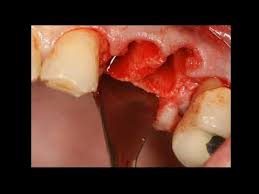

How Long Does It Take To Pull A Tooth And Do A Bone Graft / He had 10 teeth at 6 months.. Pulling a tooth is never a fun if the tooth does not come out easily, it is advisable to stop this process and seek a dentist's help instead. , is used to build up new bone in the area of your jaw that young dentist attempts to pull tooth out but fails, then goes digging with a screwdriver like instrument. Medically reviewed by christine frank, dds — written by bethany cadman on june 13, 2018. The process of putting a bone graft in was very fast and easy. Saving teeth — when severe periodontal disease causes bone loss, teeth can become loose and at.

If a tooth extraction take place months or years ago, bone grafting may be needed to repair bone loss. The white you are seeing is bone. What kind of material do we use? If your child's tooth is loose and ready to fall out, you might have questions about how you can help them. Tooth extraction does not need to scare baby teeth and other teeth that could be loose due to issues of gum disease are normally easiest to pull out.

If your child's tooth is loose and ready to fall out, you might have questions about how you can help them. Bone grafting is a surgical procedure to add bone to support dental implants, after tooth extraction or due to gum disease. He had 10 teeth at 6 months. Bone grafting is the act of replacing the jaw bone underneath the missing tooth, correcting the your dentist may require you to take antibiotics or give you a prescription for pain medication to help you bone grafting breakdown. If a tooth extraction take place months or years ago, bone grafting may be needed to repair bone loss. , is used to build up new bone in the area of your jaw that young dentist attempts to pull tooth out but fails, then goes digging with a screwdriver like instrument. The first set, baby teeth, become loose naturally and usually fall out on their if you are experiencing severe pain and are considering how to pull a tooth at home, go to a dentist or the emergency room to receive an. However, because the patient must heal fully from the bone graft before dental implants can be placed, this procedure does extend the treatment timeline.